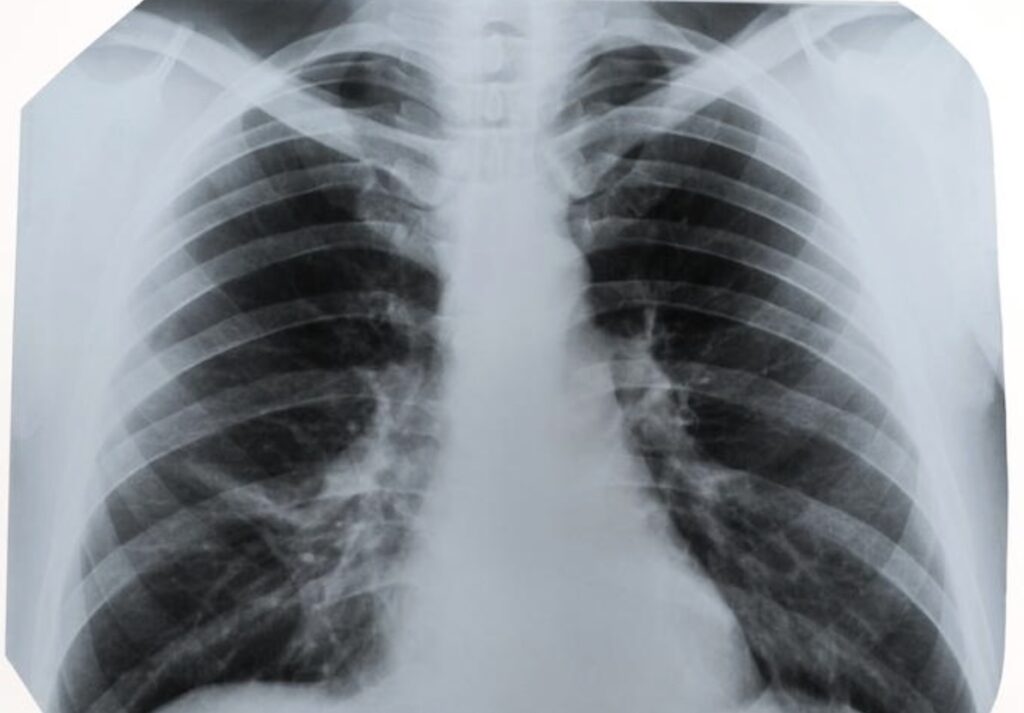

L’augmentation des cas s’explique par la hausse du tabagisme chez les femmes entre les années 1970 et 2000. Les effets de cette évolution se manifestent aujourd’hui : il faut souvent plusieurs décennies pour que les cancers induits par le tabac apparaissent. Résultat, près de 20.000 nouveaux cas sont diagnostiqués chaque année chez les femmes, avec une progression de plus de 4 % par an. Chez les hommes, le nombre de cas se stabilise. Selon des pneumologues et oncologues spécialisés, les femmes développent ce cancer plus tôt et avec un niveau de consommation parfois inférieur à celui des hommes, en raison d’une sensibilité accrue aux substances toxiques de la fumée.

Il n’existe actuellement aucun dépistage national, mais un changement se prépare. L’Institut national du cancer (INCa) a lancé un programme pilote baptisé IMPULSION, impliquant 20.000 fumeurs et ex-fumeurs de 50 à 74 ans. L’objectif : détecter le cancer avant l’apparition des symptômes, grâce à des scanners thoraciques à faible dose réalisés à un an d’intervalle, puis tous les deux ans. Un dépistage précoce associé à l’arrêt du tabac pourrait réduire significativement la mortalité. Selon les données publiées, le risque de décès diminuerait d’environ 38 %.